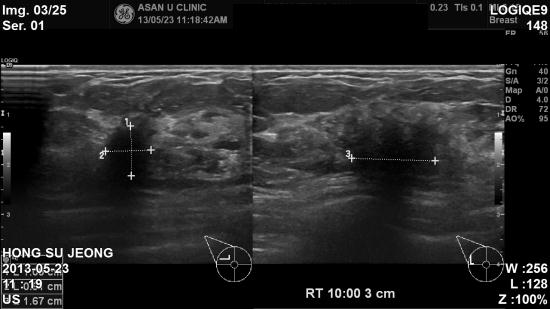

우측 유방에 멍우리가 있어 내원하신분으로,

촉진시 우측 10시 방향 2cm 만져지는 멍우리있었습니다.

본원 초음파 시행 후, 조직검사 진행하였습니다.

조직검사 결과상 유방암으로 진단되었습니다.